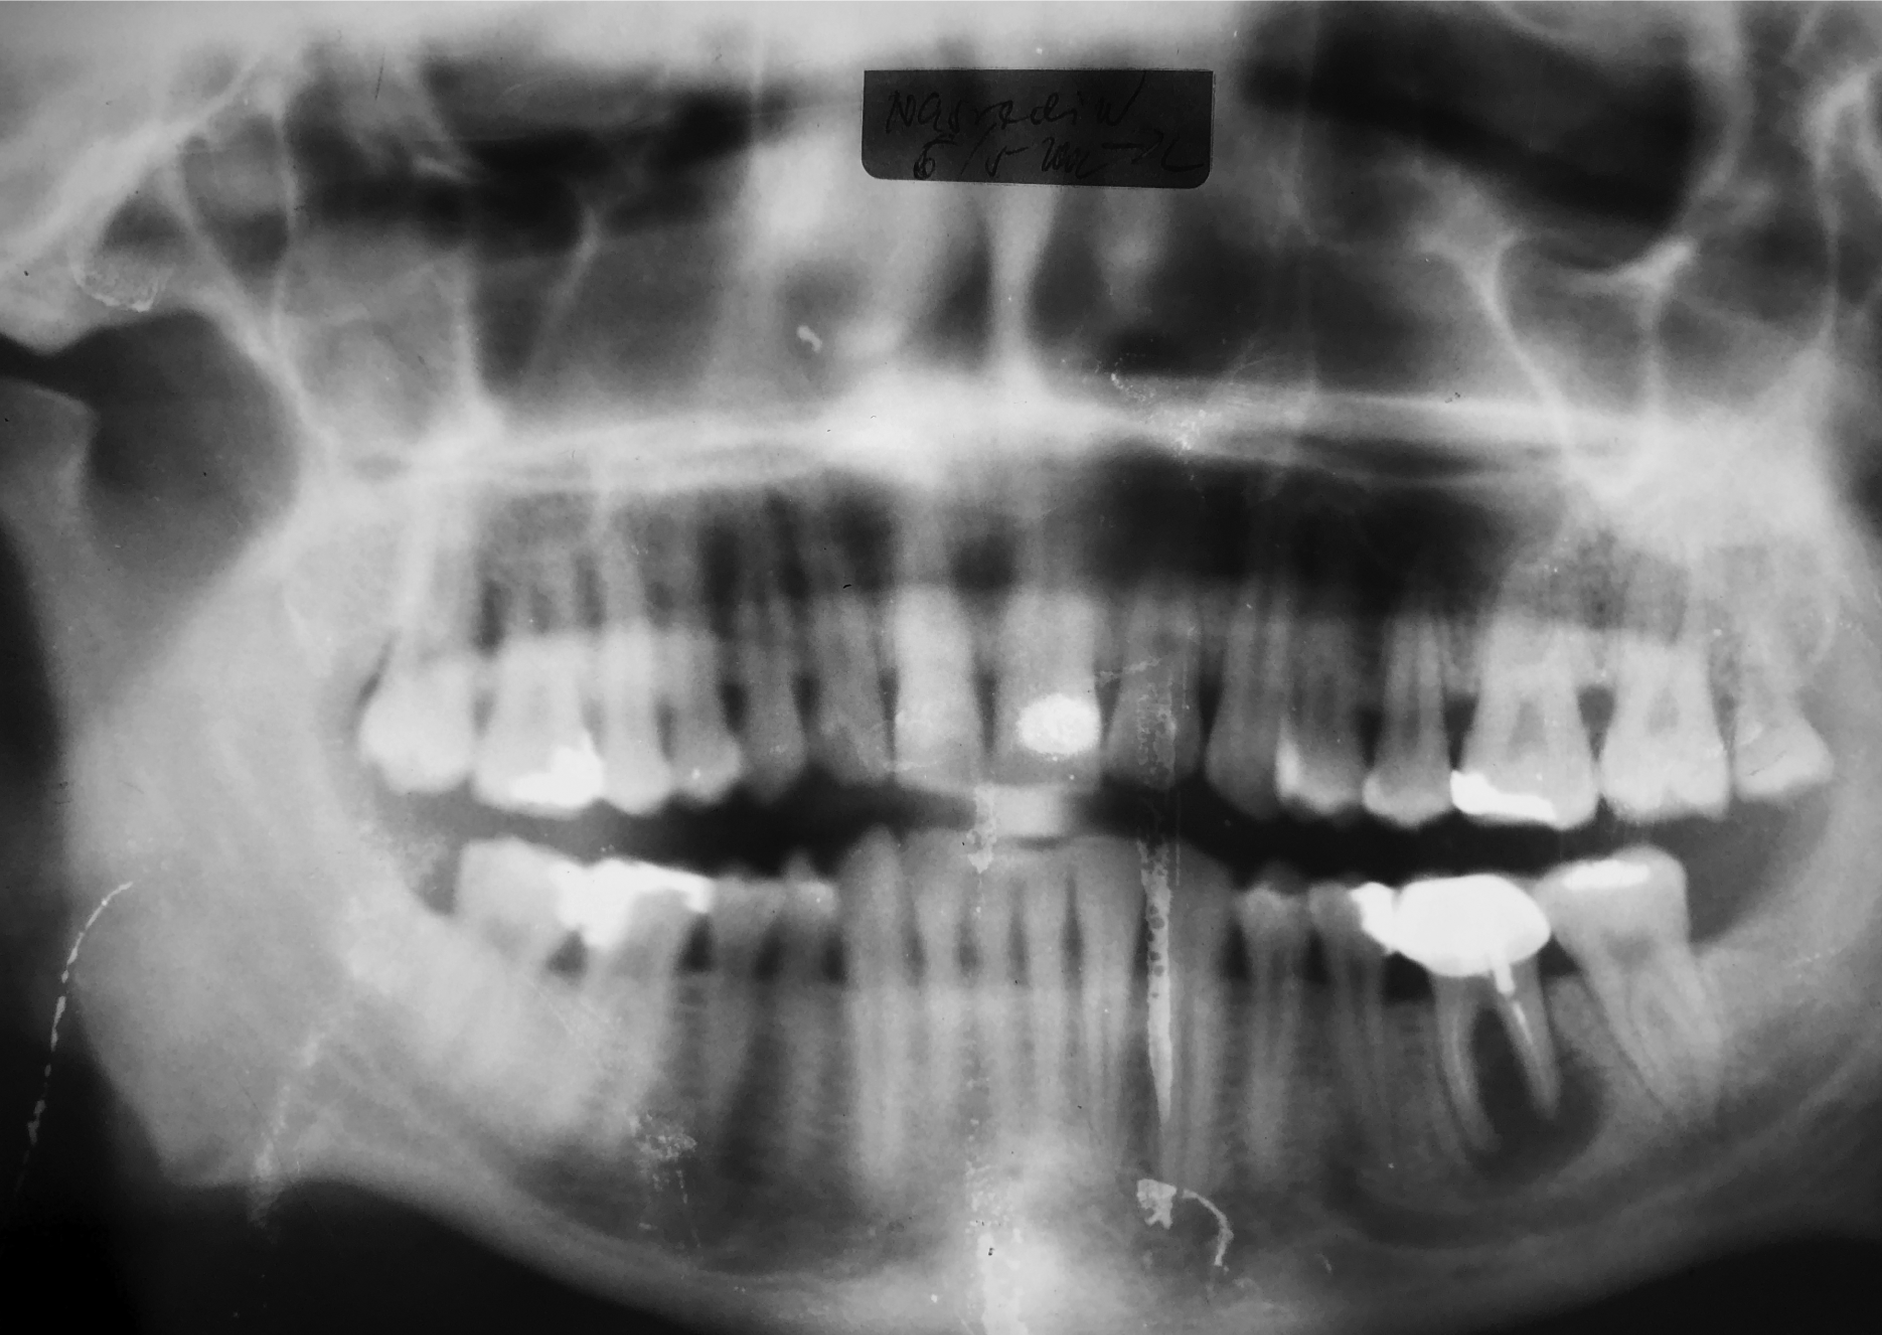

Ausgangsituation im Mai 2002 in Regio 36. Der Zahn wurde folgend extrahiert und der Defekt ordentlich exkochleiert.

Röntgenaufnahme des ausgeheilten Regio 36 nach dem Eingriff ohne Verwendung von Knochenersatzmaterialien von Juni 2003. Hinsichtlich der Lückenbreite und dem Alveolarknochenvolumen wurden zwei Implantate mit Ø 2,9 mm eingesetzt.